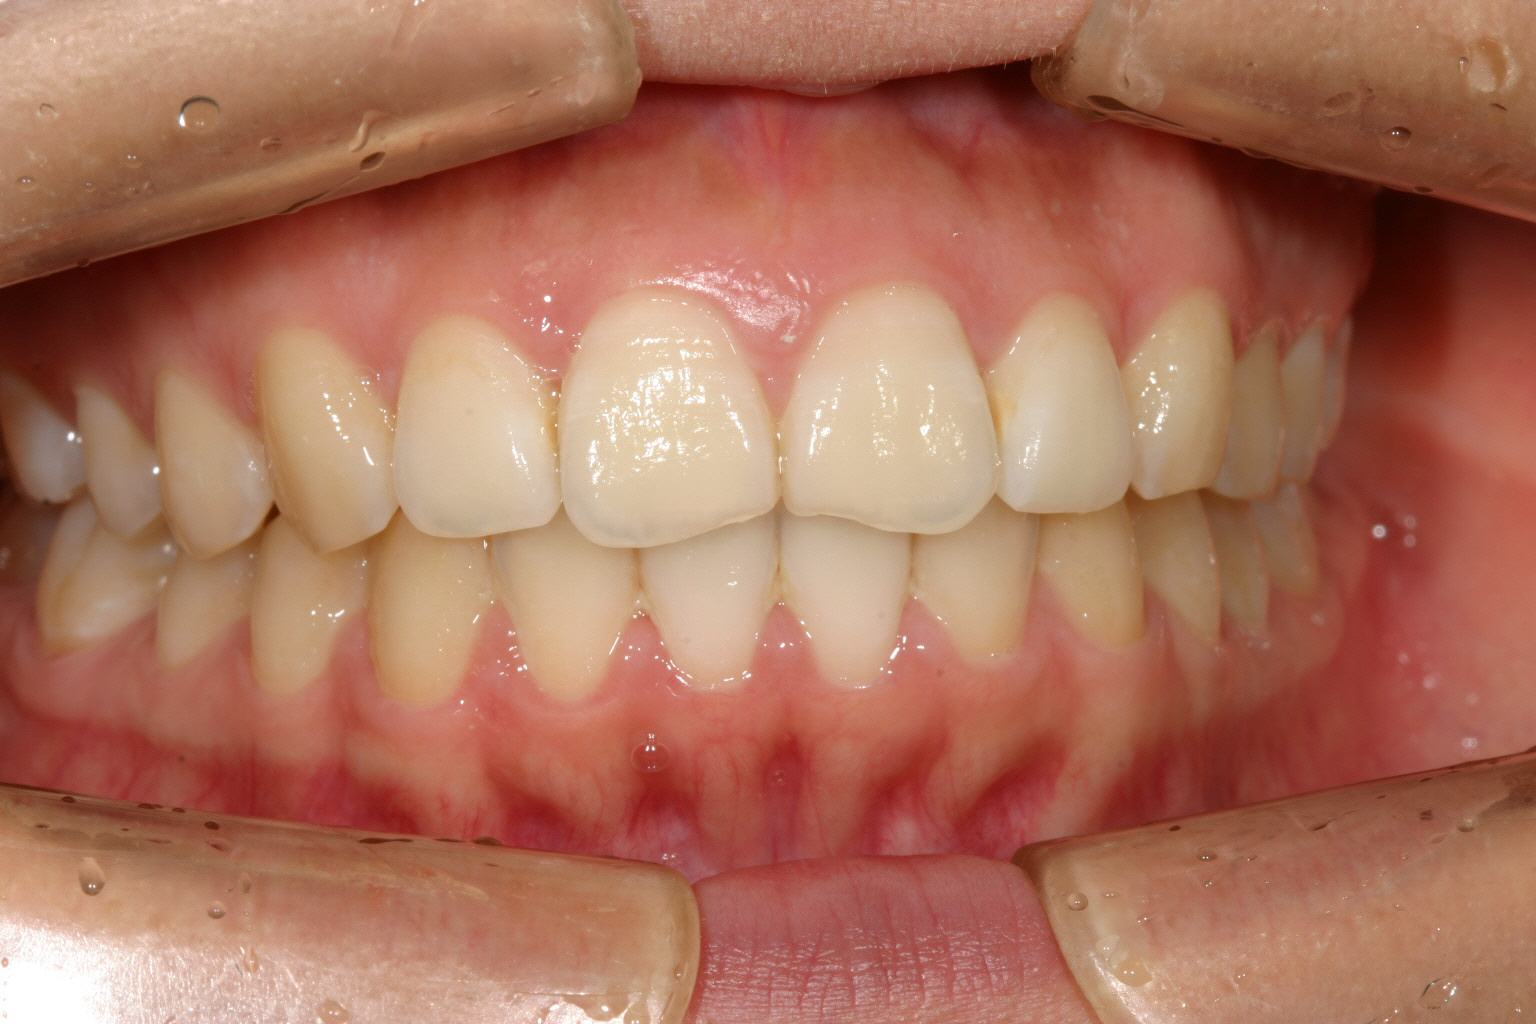

綺麗に改善しました。

翼状捻転改善しましたら出加減も改善しました。